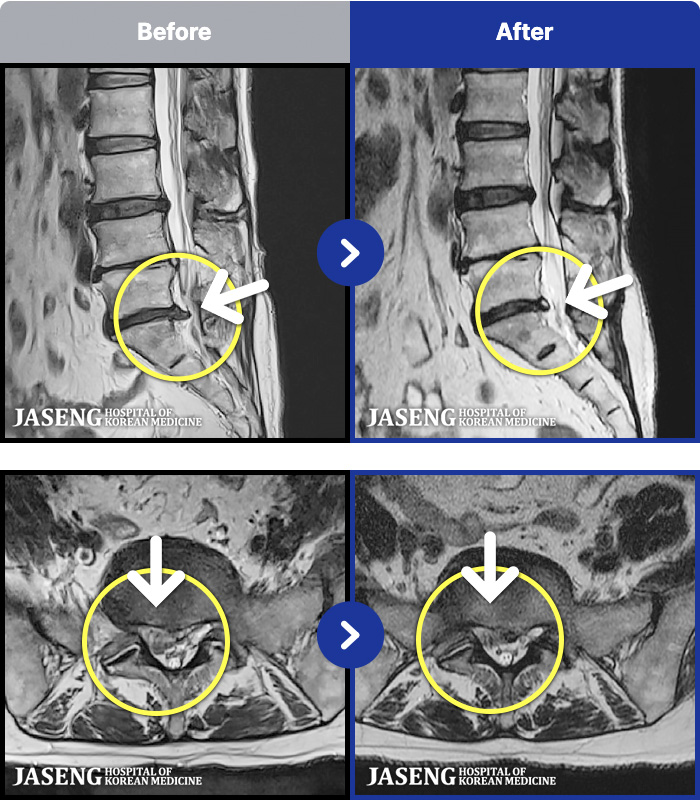

ȯںп Ǹ ǿ ԿǾ, ο ġ ۿ Ƿ ġḦ Ͻñ ٶϴ.